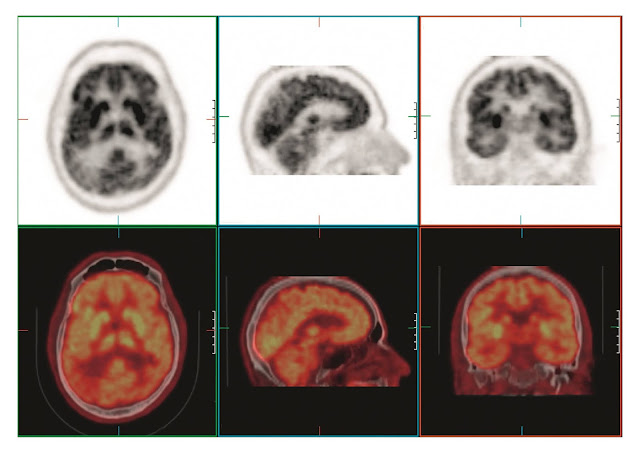

Positron emission tomography (PET) scanning is designed to assess the distribution of tracers labeled with positron-emitting nuclides, such as carbon-11 (11C), nitrogen-13 (13N), oxygen-15 (15O), and fluorine-18 (18F). Fluorodeoxyglucose (FDG), a glucose analogue labeled with 18F, can cross the blood-brain barrier. The metabolic products of FDG become immobile and trapped where the molecule is first used, thereby permitting FDG to be used to map glucose uptake in the brain.

This is a valuable tool for investigating subtle

physiological processes related to neurological

diseases. The distribution of FDG can be localized and reconstructed using

standard tomographic techniques that show the tracer distribution through- out

the body or brain. In this example of axial, sagittal, and coronal views, the

transmission measurement and correction was performed immediately following PET

acquisition using a 16-slice CT unit. The PET and CT images were automatically

fused by anatomical coregistration software (shown as colored images).